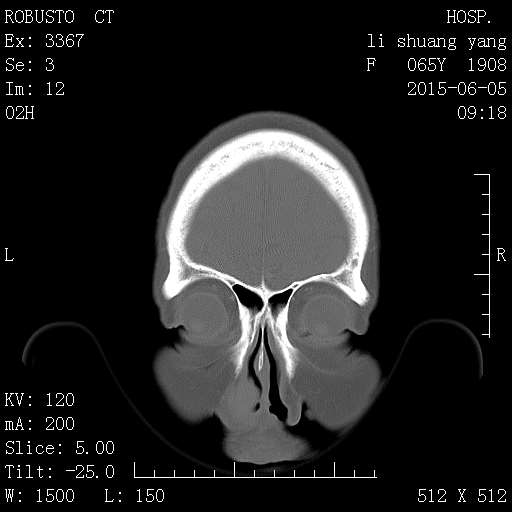

CT50568:鼻

1)左侧鼻前庭囊肿。2)双侧下鼻甲肥大。

1)左侧鼻前庭囊肿。2)双侧下鼻甲肥大。支持!